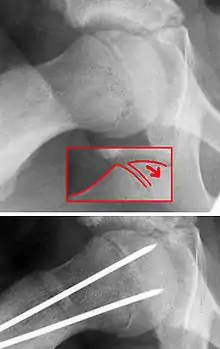

X-ray showing a slipped capital femoral epiphysis, before and after surgical fixation.

The diagnosis requires x-rays of the pelvis, with anteriorposterior (AP) and frog-leg lateral views.[11] The appearance of the head of the femur in relation to the shaft likens that of a "melting ice cream cone", visible with Klein's line. The severity of the disease can be measured using the Southwick angle.

Treatment

The disease can be treated with external in-situ pinning or open reduction and pinning. Consultation with an orthopaedic surgeon is necessary to repair this problem. Pinning the unaffected side prophylactically is not recommended for most patients, but may be appropriate if a second SCFE is very likely.[11]

Once SCFE is suspected, the patient should be non-weight bearing and remain on strict bed rest. In severe cases, after enough rest the patient may require physical therapy to regain strength and movement back to the leg. A SCFE is an orthopaedic emergency, as further slippage may result in occlusion of the blood supply and avascular necrosis (risk of 25 percent). Almost all cases require surgery, which usually involves the placement of one or two pins into the femoral head to prevent further slippage.[12] The recommended screw placement is in the center of the epiphysis and perpendicular to the physis.[13] Chances of a slippage occurring in the other hip are 20 percent within 18 months of diagnosis of the first slippage and consequently the opposite unaffected femur may also require pinning.

The risk of reducing this fracture includes the disruption of the blood supply to the bone. It has been shown in the past that attempts to correct the slippage by moving the head back into its correct position can cause the bone to die. Therefore the head of the femur is usually pinned 'as is'. A small incision is made in the outer side of the upper thigh and metal pins are placed through the femoral neck and into the head of the femur. A dressing covers the wound.